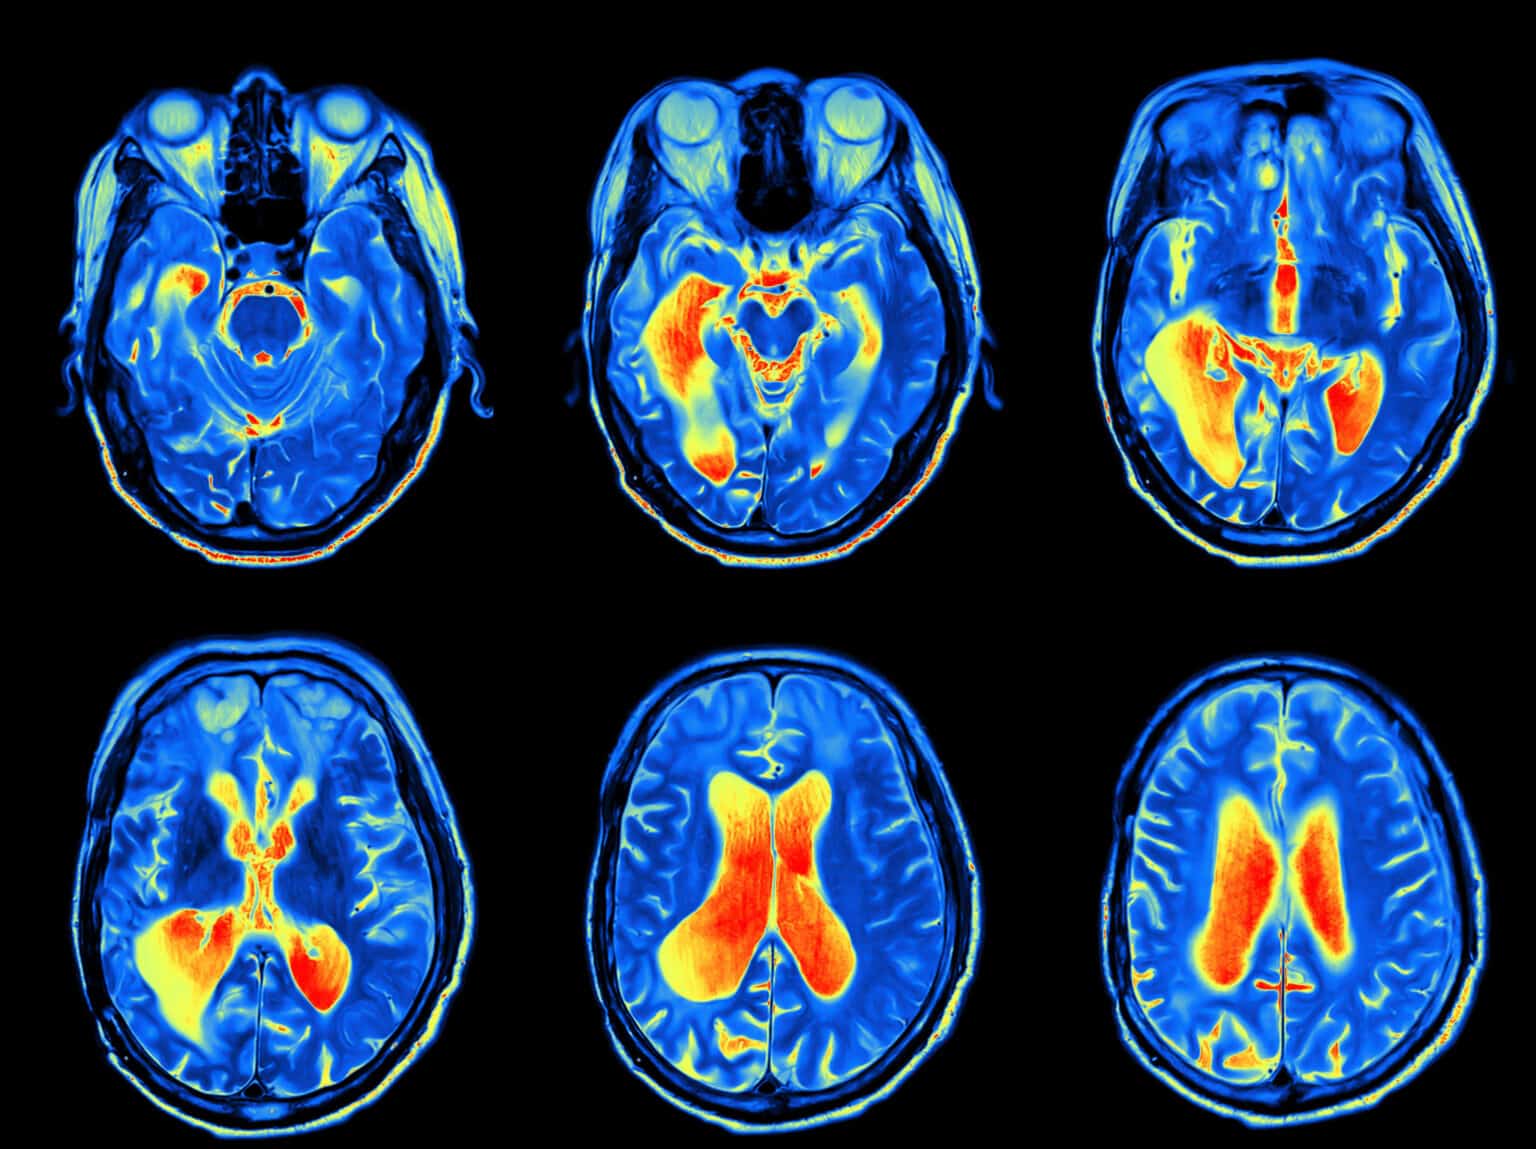

- Imaging: CT (computerized tomography) or MRI (magnetic resonance imaging) determine if there is infection, tumor, bone fracture, or other abnormality in the area of the facial nerve.